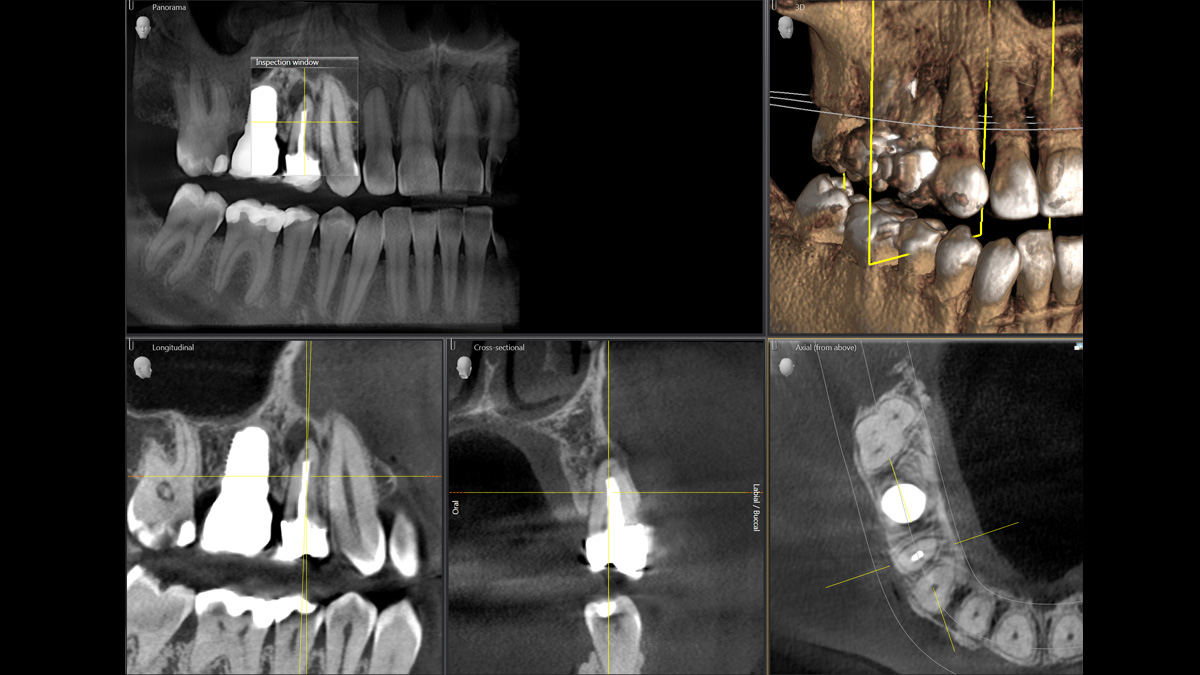

Der 2D/3D Power Performer Orthophos SL ist eine großartige Wahl für alle, die einfach mehr wollen. Der integrierte Direct Conversion Sensor (DCS) wurde für anspruchsvolle Bildqualitätsstandards entwickelt und bietet detaillierte Daten. Der intelligente Autofokus liefert automatisch fokussierte Panoramabilder mit hervorragender Gesamtschärfe. Orthophos SL bietet höchsten Bedienkomfort durch automatische Positionierung, eine anwenderfreundliche, intuitive Bedienung mit dem EasyPad und ein individuell einstellbares Umgebungslicht für ein exklusives Erscheinungsbild.

Der Direct Conversion Sensor erfüllt besonders hohe Standards für die 2D-Bildgebung

Der Autofokus erzeugt aus mehreren tausend Einzelbildern automatisch eine beeindruckende scharfe Panorama-Röntgenaufnahme

Mit dem Low Dose-Modus erhalten Sie 3D-Bilder im Dosisbereich einer 2D-Röntgenaufnahme. Im HD-Modus werden während eines einzelnen Umlaufs mehr als 800 Einzelbilder aufgenommen und zu einem 3D-Volumen mit bis zu 80 μm zusammengeführt. Der Vorteil für Sie: rauschärmere Aufnahmen in hoher Auflösung

Der Direct Conversion Sensor (DCS) hat den Standard der Panorama-Bildgebung neu definiert. Röntgenstrahlen werden direkt in elektrische Signale umgewandelt – im Gegensatz zu herkömmlichen Systemen gibt es keinen Signalverlust durch Lichtumwandlung, was eine verbesserte Bildgebung ermöglicht. Das Ergebnis sind Bilder mit einer sehr hohen Schärfe, selbst bei niedriger Dosis.

Eine Röntgenaufnahme muss sofort diagnostizierbar sein. Der Autofokus hilft dabei erheblich. Orthophos SL erfasst mehrere tausend Einzelbilder in einem Zyklus und erkennt automatisch scharfe Bereiche, um ein gleichmäßig scharfes Gesamtbild zu erzeugen. Der intelligente Autofokus erfordert keine manuellen Arbeitsschritte vor und nach der Erfassung.

Ein breites Spektrum an Volumengrößen für verschiedene diagnostische und klinische Anforderungen von Ø 5 × 5,5 cm bis Ø 11 × 10 cm